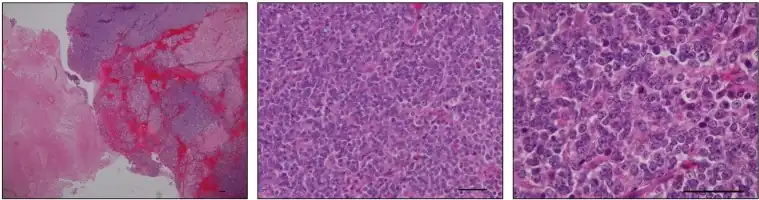

Первичная опухоль (саркома) с химерностью CIC-DUX4 у 9-летней девочки. Окраска гематоксилином и эозином. Фрагмент иллюстрации из Nakai et al., 2019.[10]